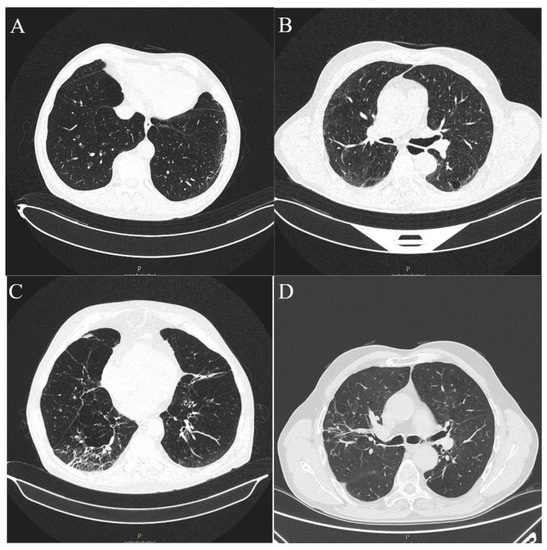

Figure 2.

Axial MSCT scans of pretreatment lung parenchyma demonstrating other radiological findings found in HNSCC patients. (A) Healthy lung parenchyma in lung window reconstruction. (B) Advanced centrilobular emphysema affecting all lung lobes seen as hyperlucent lung parenchyma, typical finding for heavy smokers in lung window reconstruction. (C,D) Same patient with lung metastasis which presents as soft tissue density, well circumscribed, round lesion with significant contrast enhancement and central necrosis in lung window reconstruction (C) and soft tissue window with intravenous contrast (D).

Analysis of lung MSCT found that the most frequently reported radiological findings on MSCT scans were centrilobular (n = 34, 30%) and paraseptal (n = 36, 31.9%) emphysema, centrilobular nodules (n = 21, 18.6%), pleural plaques (n = 2, 1.8%) and calcification of coronary arteries (n = 91, 81.4%). There was no significant statistical difference in reported radiological findings between the ILA and non-ILA groups, except pleural plaques, which were reported only in the ILA group (p = 0.0165). Lung metastasis was observed in nine patients (7.96%) with no statistical difference between the groups (p = 0.341) (Table 2, Figure 2).